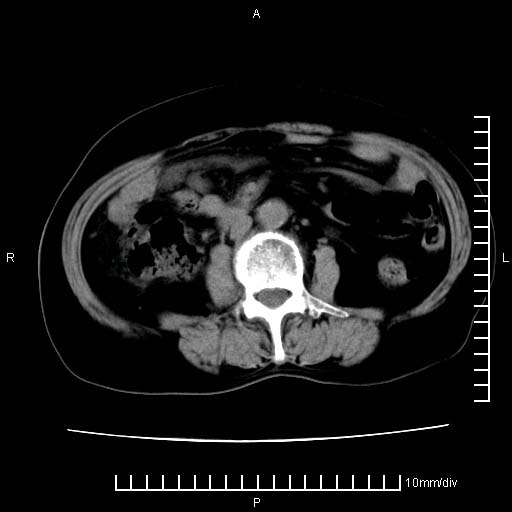

下腹疼痛2月,加重并呕吐2天,下腹压痛,反跳痛。白细胞1万2.

下腹至盆腔较大包块,与邻近肠管关系密切,下腹疼痛2月,加重并呕吐2天,下腹压痛,反跳痛。白细胞1万2.

由于没有做肠道准备很难分清是哪根肠管,但看位置考虑为升结肠回盲部的问题,我首先考虑化脓性阑尾炎,不除外结肠癌合并感染化脓。建议做增强进一步明确。

不知道大家可要注意下腹腔小肠旁不规则结节状灶,部分钙化,是否要考虑小肠腺癌.盆腔包块可能考虑脓肿.